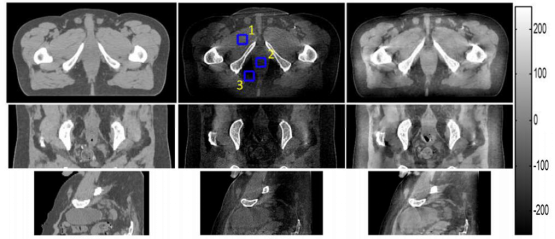

统一重建框架重建结果图